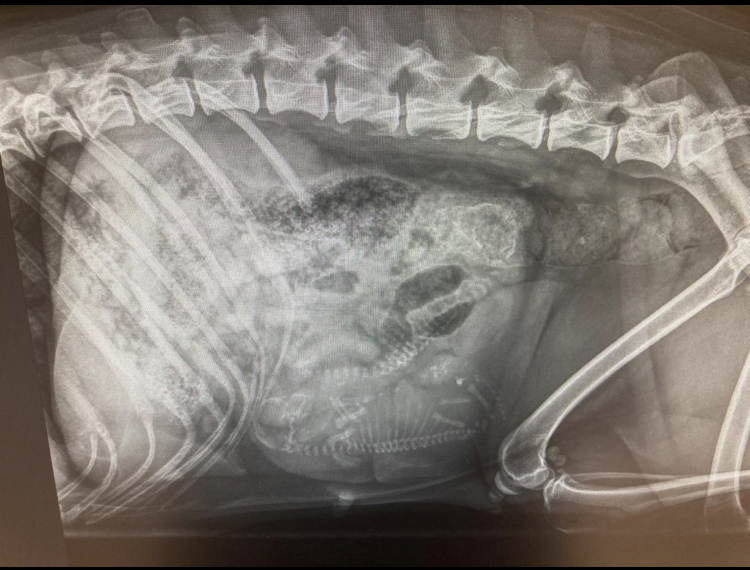

Kajalle tehtiin ultraäänitutkimus tiineyden kestettyä 4 viikkoa. Ultrassa näkyi vain 2 pentua, joten halusin vielä röntgenkuvata Kajan myöhemmin pentumäärän varmistamiseksi. Kahden pennun pentueessa on kuitenkin synnytysvaikeuksien riski hieman suurempi, joten halusin tietää etukäteen tarkemman pentumäärän. Röntgenkuvissakin näkyi kuitenkin vain se 2 pentua, mutta toivotaan, että kaikki sujuu hyvin.

Röntgenkuvaus tehtiin hereillä tiineyden vuoksi, joten kuva ei ole aivan suora ja takajalatkin ovat vähän tiellä (syy, miksi röntgenkuvat tehdään yleensä rauhoitettuna, on juurikin se, että kuvien laatu ja sitä kautta ns. "diagnostinen arvo" olisivat mahdollisimman hyvät). Pentumäärän laskemiseksi laatu on aivan riittävä. Itse emä otti tilanteen rennosti =)